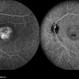

- Fundus autofluorescence imaging of a patient with autosomal recessive Best disease